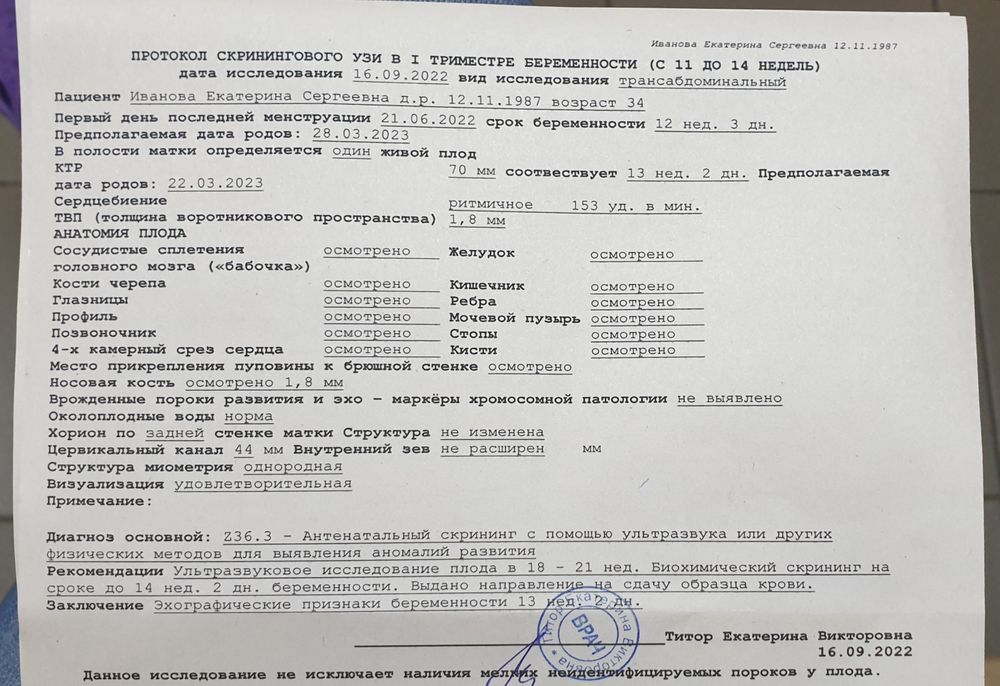

Первый скрининг

Что то переживаю...Узи делали в12,3. По размерам ктр 70 мм на 13,2 дн. Твп 1,8мм. А вот носовая кость 1,8мм очень смущает,маленькая... У кого нибудь было так же. Результаты крови надеюсь будут в понедельник. Не могу дождаться.